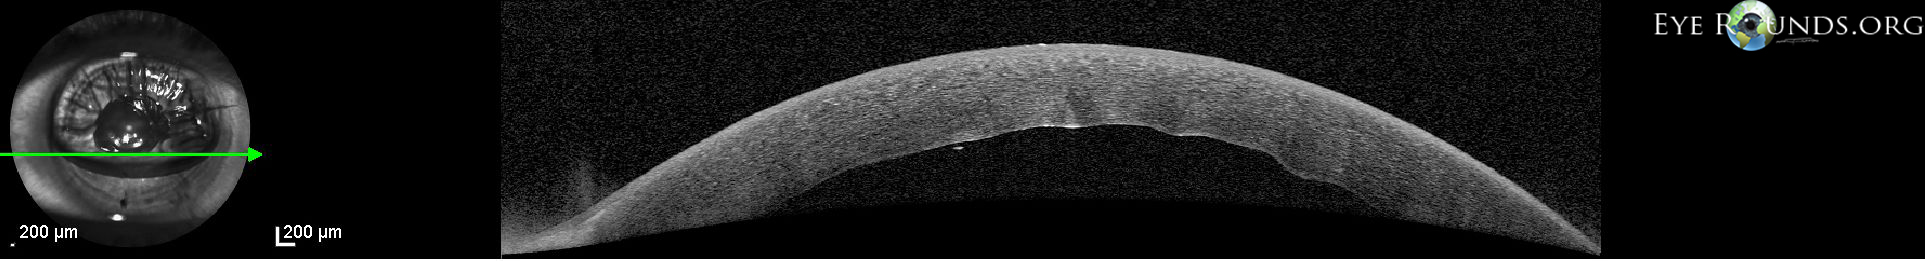

Corneal edema with Descemet's membrane folds after DMEK

TThis patient had residual corneal edema with prominent Descemet's membrane folds visible on the posterior corneal surface on her first postoperative day after undergoing Descemet's membrane endothelial keratoplasty (DMEK). In the first photograph, the anterior chamber is 70% filled with SF6 gas and a superotemporal limbal suture can be seen. Anterior segment OCT verifies that the lenticule is in place and also shows the folds on the posterior corneal surface. After several days, the corneal edema eventually cleared and guttae were visible centrally in the graft tissue, consistent with Fuchs' endothelial dystrophy of the donor. These guttae are visible in the second photograph and this is likely the cause for delayed corneal clearing. Despite this, the patient still achieved 20/20 acuity.